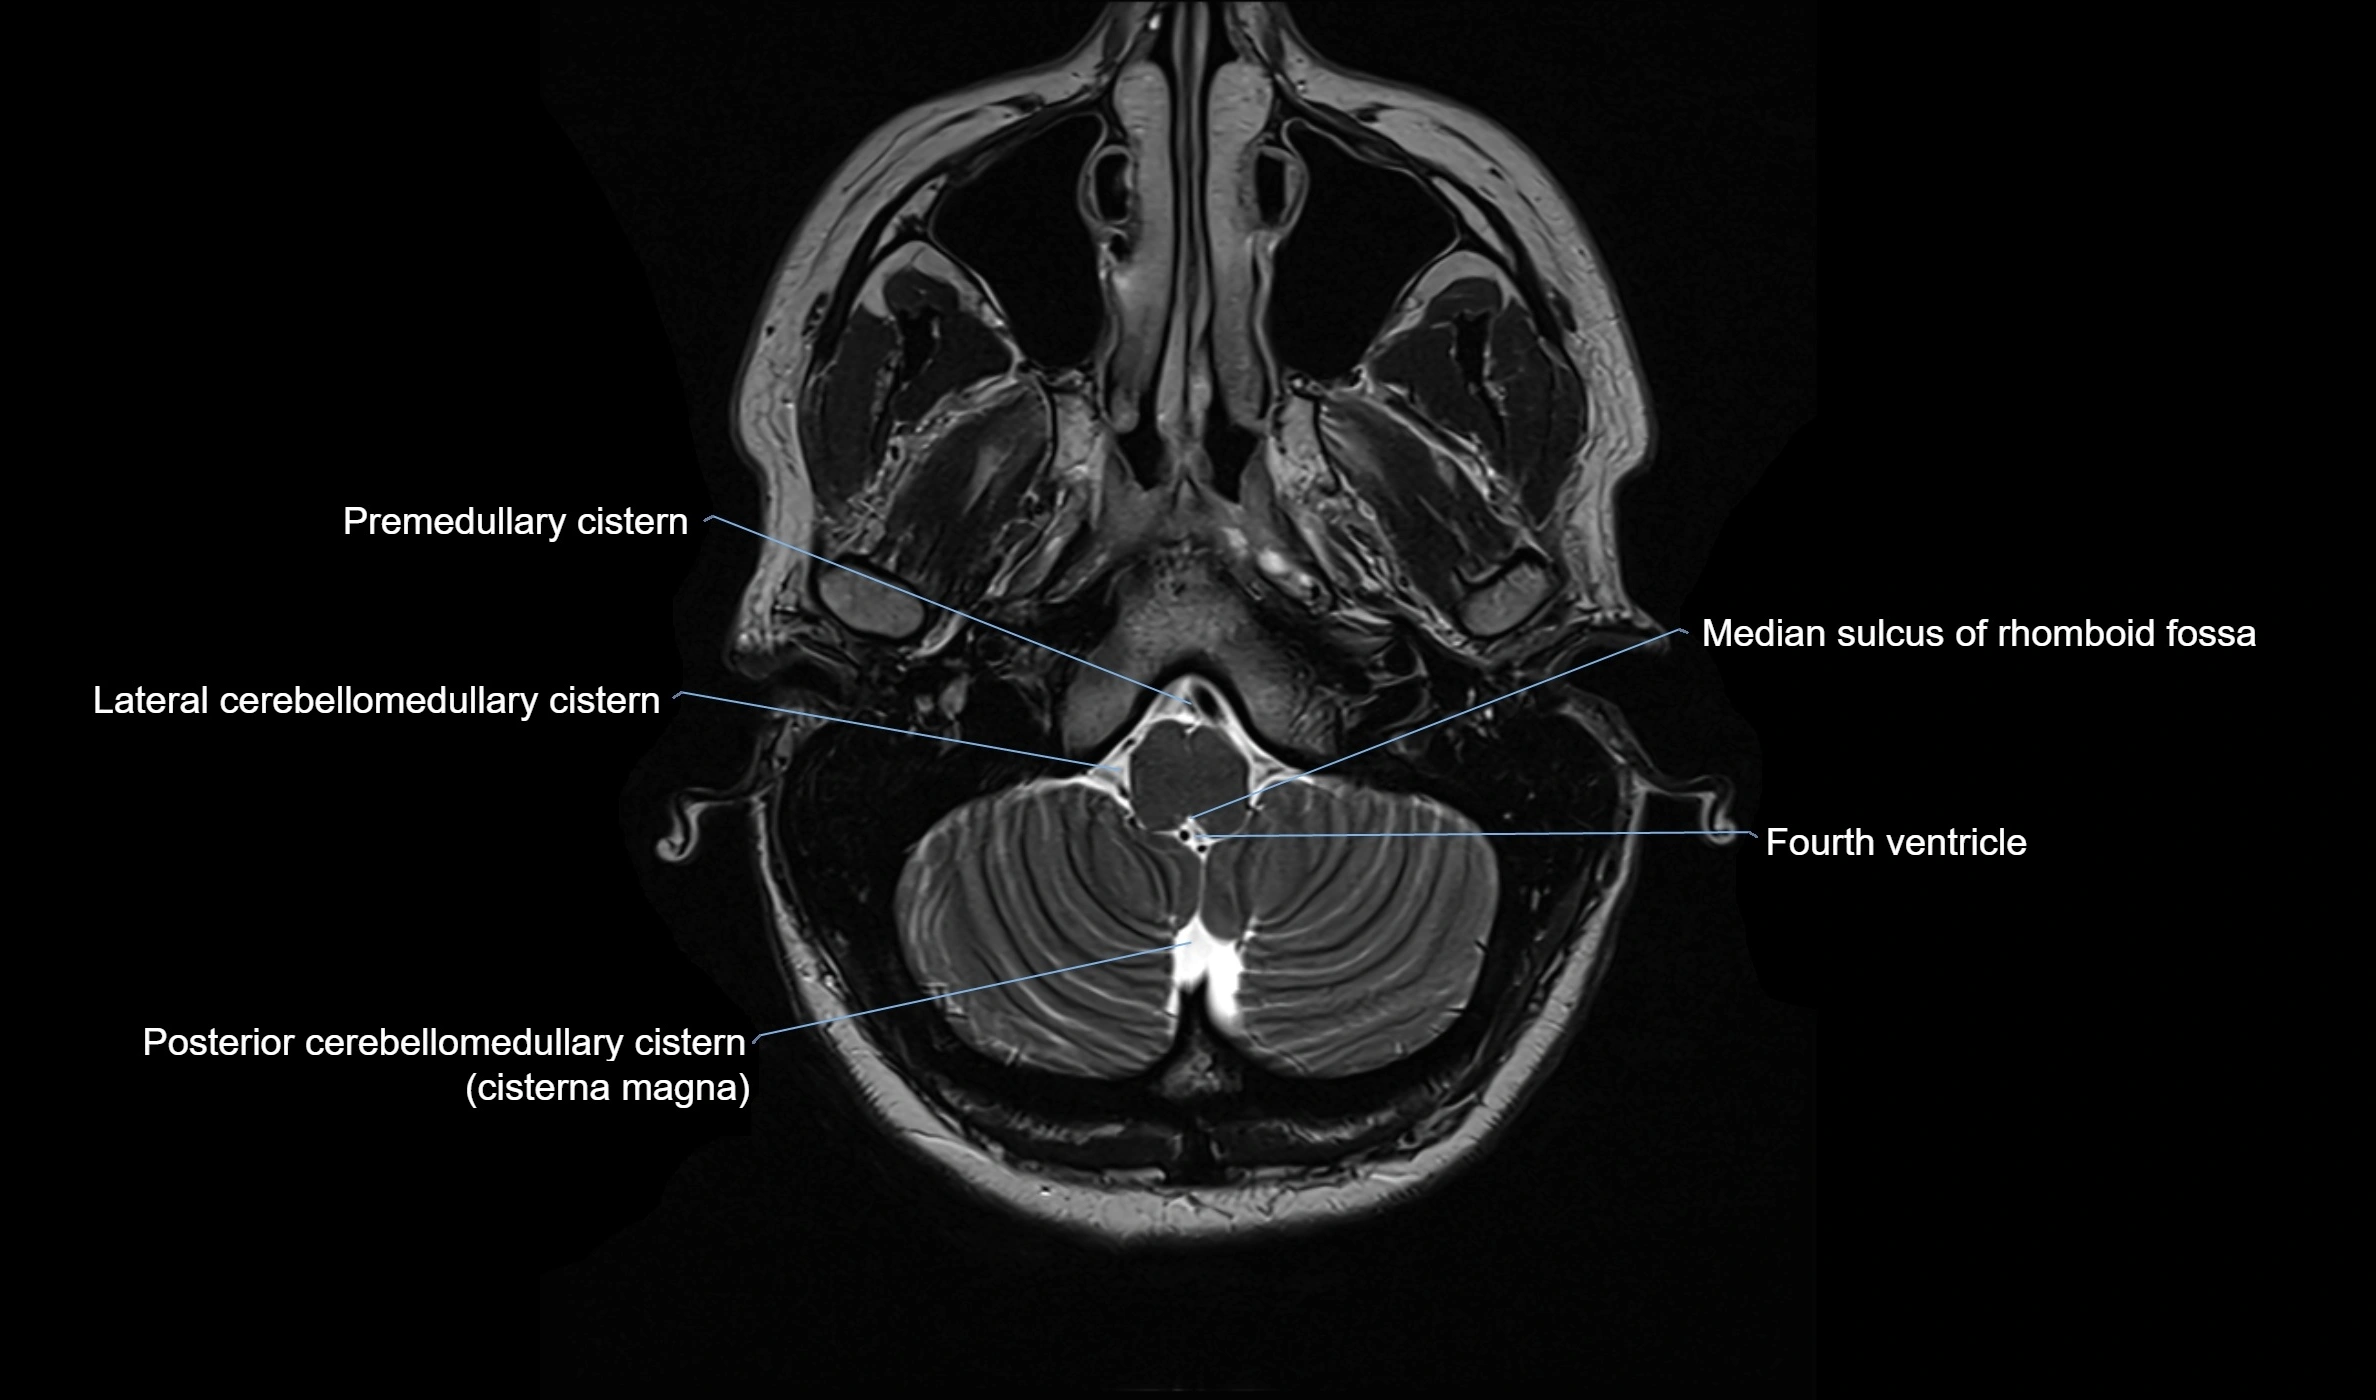

CT image

image